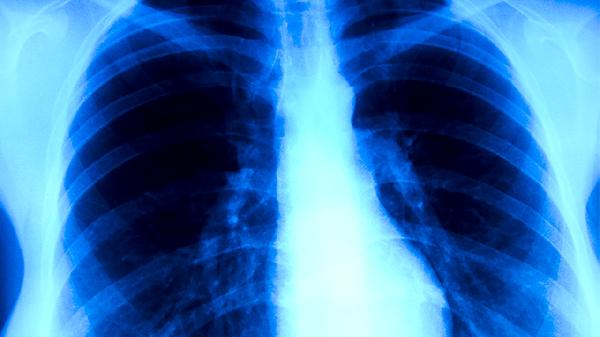

治疗肺癌的靶向药主要有吉非替尼片、盐酸埃克替尼片、奥希替尼片、克唑替尼胶囊、贝伐珠单抗注射液等。靶向药物需根据基因检测结果选择,建议在医生指导下规范使用。